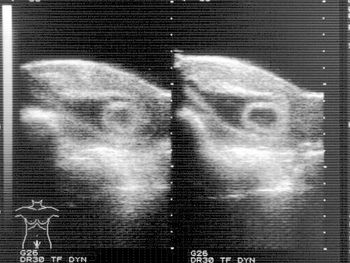

In February 1988, the patient, a 26-year-old married woman, experienced moderate vaginal bleeding. She contacted her gynecologist, who referred her to an ultrasound clinic for a sonographic workup.